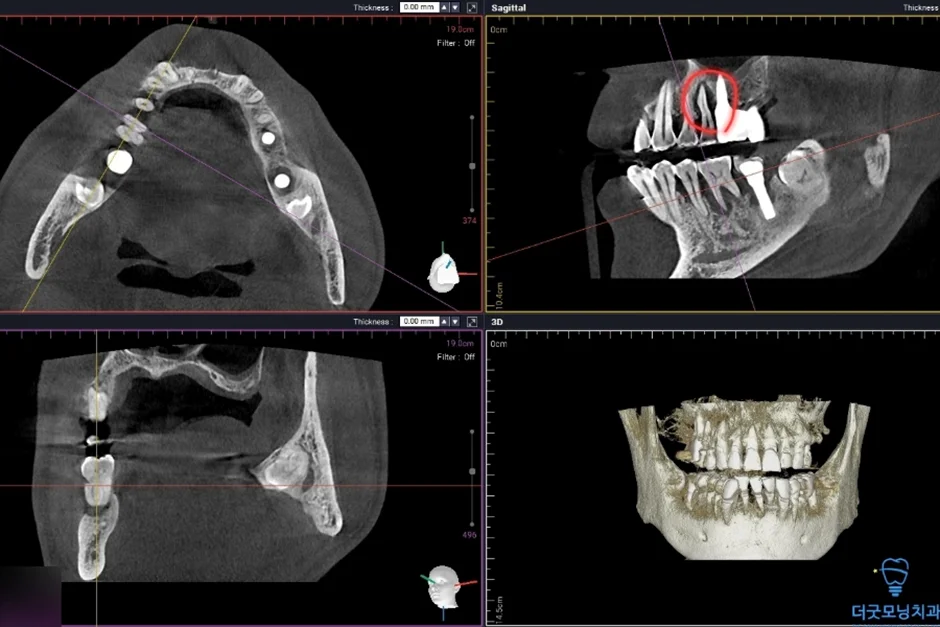

2. 검진 결과 — 파노라마 엑스레이 & CT 분석

먼저 파노라마 엑스레이와 CT를 통해 구강 전체 상태를 확인하였습니다.

상악동이 많이 함기화되어 있어 상악동 골이식(치조정 접근 상악동 거상술)이 반드시 필요한 상태였습니다. CT 확인 결과 가용골이 매우 부족한 것이 명확히 확인되었습니다.

임플란트 주위염이 발생하여 기존 임플란트를 제거하고 재수술이 필요한 상태였습니다. CT 상 신경관까지 어느 정도 거리가 확보되어 재수술은 무리 없이 진행 가능하였습니다.

■ 1차 수술 (오른쪽)

미다졸람을 투여 후 편안하게 수면에 드신 상태에서 오른쪽 임플란트 수술을 먼저 진행하였습니다.

아래 임플란트 제거한 사진

임플란트를 치조정 접근 상악동 거상술을 통해 3개의 임플란트가 식립된 사진

하악의 임플란트 주위염 부위는 기존 임플란트를 제거하고 재식립하였으며, 상악의 경우 치조정 접근 상악동 거상술을 통해 3개의 임플란트를 안정적으로 식립하였습니다.